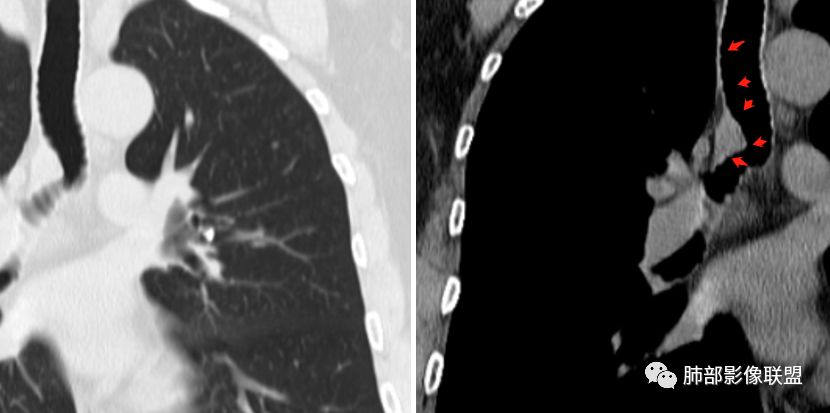

病例小结      气管神经鞘瘤属于罕见的气管良性肿瘤,一般气管良性肿瘤或腔内或腔外生长的结节样改变,恶性肿瘤呈腔内外生长,但本例肿块向腔外生长,呈“冰山样改变”,即肿瘤的腔内部分较小而腔外部分较大,无周围组织侵犯。因此肿瘤腔内外生成不能作为鉴别气管良恶性肿块的绝对依据。        因此冠(矢)状位多平面观察、软骨是否破坏、气管壁有无增厚等细节观察,对于鉴别气管肿块良恶性有重要的参考性。

1.气管隆凸上右前壁不规则结节影,部分突入腔内,南边老师观察有推挤软骨环“破土而出”的形态特征。注意没有沿气管粘膜表面生长蔓延的生物学行为。

2.影像学病灶占据腔内外,但病灶边缘十分清楚。这点倾向良性。